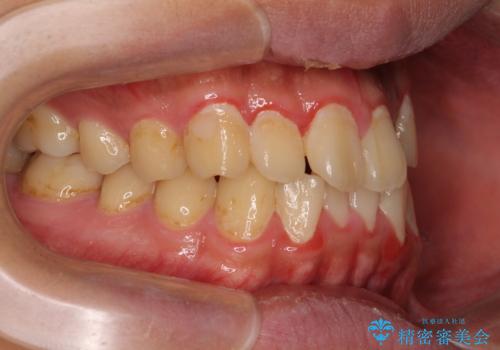

気になっていたクロスバイトは速やかに改善され、1年間で治療を終えることができました。

治療開始前は汚れが多く、全体的に歯肉が腫れていましたが、矯正治療を通して腫れも少しずつ改善されました。